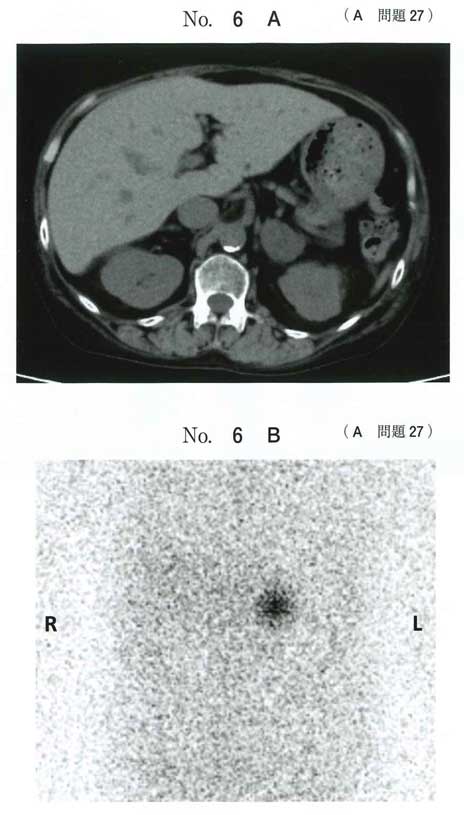

Cushing症候群ですか。満月様顔貌や水牛様肩などがキーワードですね。

副腎腺腫を摘出してコルチゾール不足になるのでdを投与するというストーリーで理解はあっていますでしょうか?